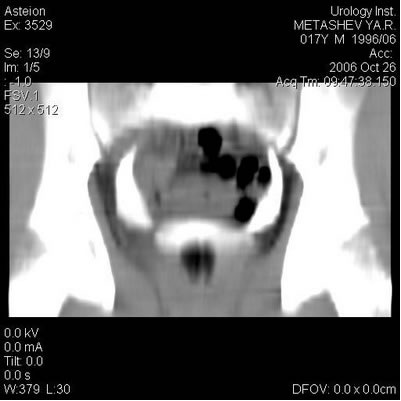

Компьютерная томография

УЗИ – Левая почка-9,7х4,1 см, т.п. 1,4

см. ЧЛС незначительно расширена: лоханка 1,0 см; верхняя

чашечка до 0,6 см. Верхняя треть мочеточника не визуализируется.

Правая почка-9,3х4,0 см, т.п. 1,4 см. ЧЛС не расширена,

верхняя треть мочеточника не визуализируется. Дополнительных

образований не выявлено. Мочевой пузырь - внутренний контур

четкий, умеренно складчатый. Толщина стенок 0,3 см. Мочеточники

в нижней трети расширены до 1,0 см.